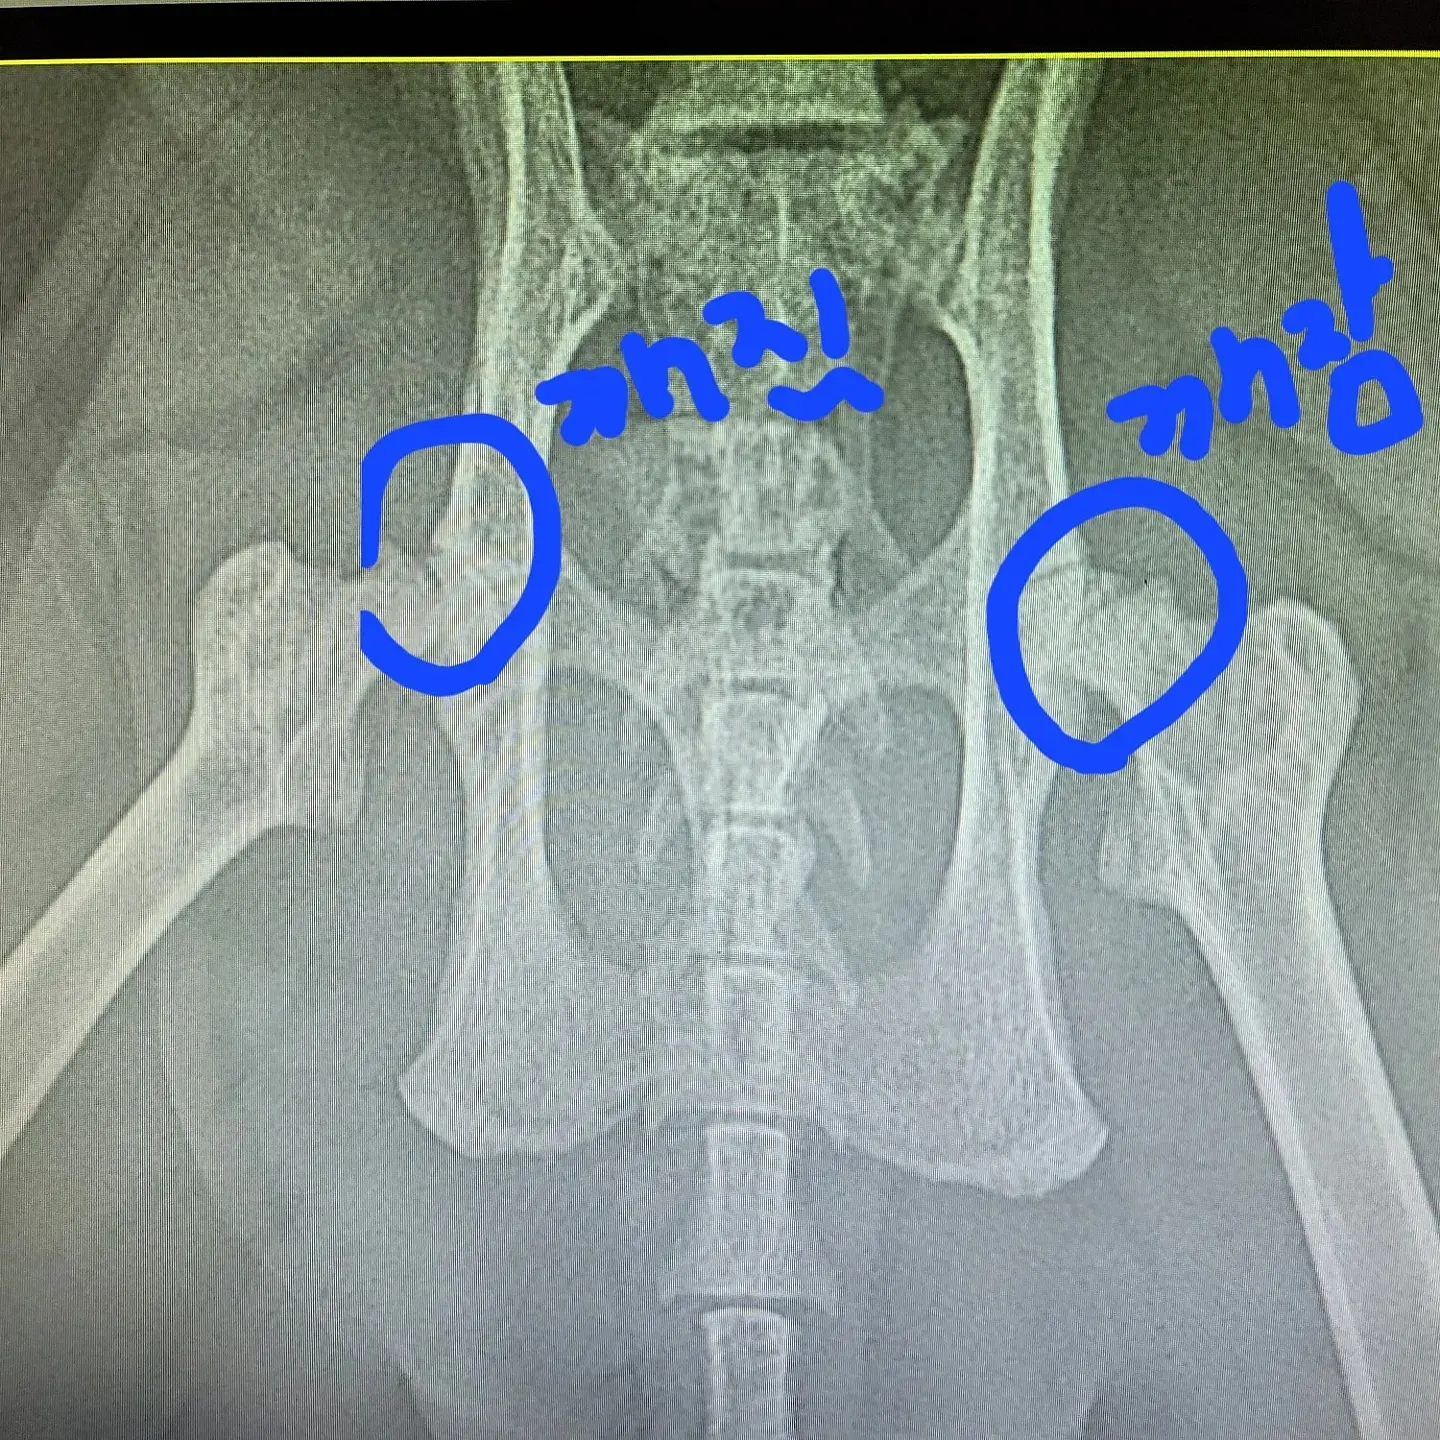

선생님들 말로는 이런 상황은 정말 드물다고 합니다..

한쪽이 깨지거나 하는 경우는 있는데 양쪽다 깨지기는 어렵다고..

아이에게 이렇게 될만한 충격이 있던 때가 있느냐며 물어보시드라고요..

저희도 생각해 보니... 캣타워에서 한번 떨어진 적이 있거든요... 지가 놀다가 등으로 떨어진거 같았는데

그때 충격이지 않을까 생각합니다. ㅜ.ㅜ

위에 있는 사진처럼 대퇴골두를 절단하는 방법!!

여기를 절단하면나중에 근육들이 생겨나면서 뼈와뼈를 잡아주어 근육이 골두의 역할을

하기 때문에 괜찮다고 합니다.